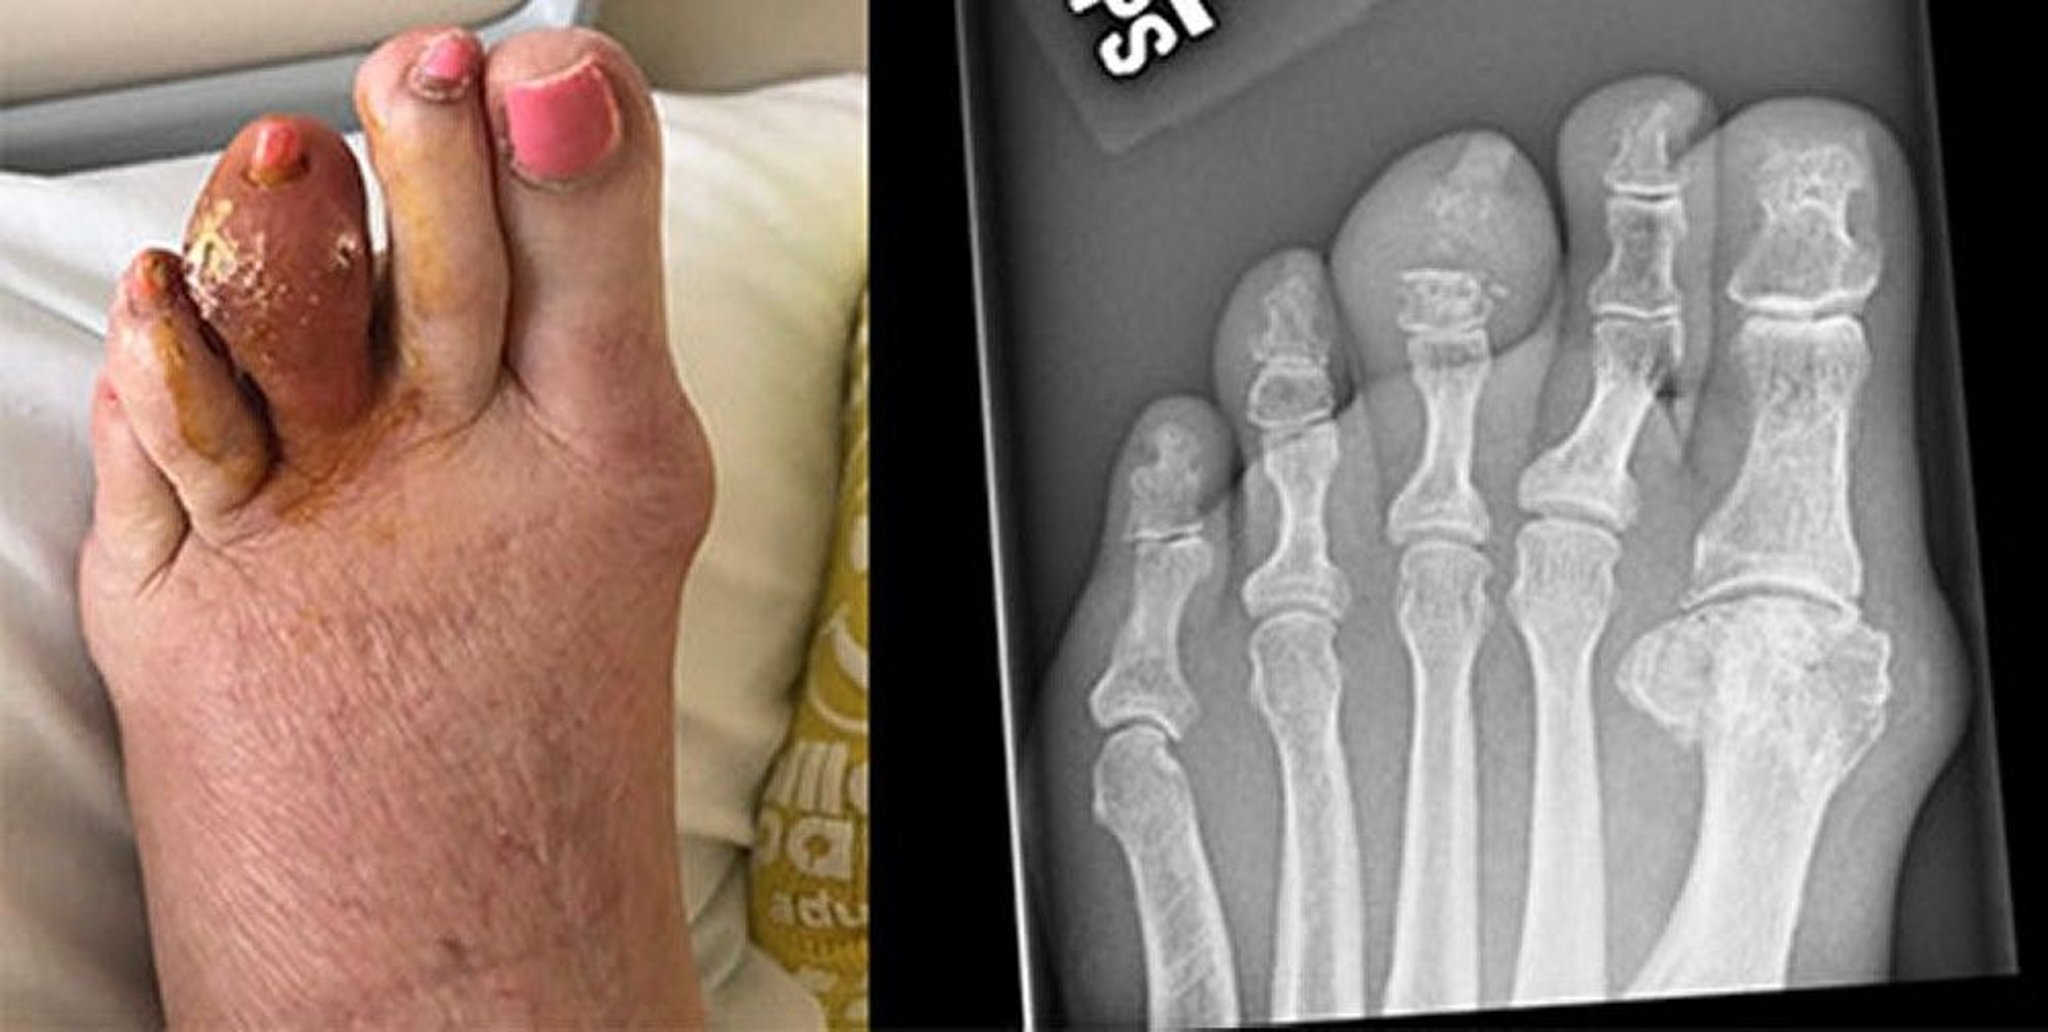

Gicht der mittleren Zehe

Dieses Foto zeigt einen großen Tophus der linken dritten Zehe, der sich aufgelöst und verhärtete Harnsäure freigesetzt hat. Die Röntgenaufnahme rechts zeigt eine Erosion der mittleren Phalanx und des distalen Interphalangealgelenks.

Images courtesy of Brian F. Mandell, MD.